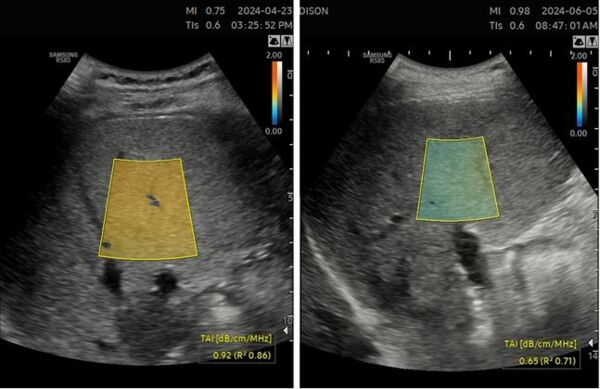

티에이아이는 간 내 지방 축적량을 수치로 정량화해 객관적으로 지방간 중등도에 대한 진단이 가능하게 하는 한편 측정 부위의 지방 침착 정도를 컬러로 시각화해 줘 진단을 돕는다. 또한 MRI에 비해 접근성과 편의성이 높으며 비침습적이라는 장점이 있다.

변영혜 삼성서울병원 교수는 “티에이아이를 통한 비침습적 검사는 간에 지방이 축적된 양을 백분율로 표시해주어 의료진이 환자와 직관적으로 소통할 수 있게 해준다”며 “지방간은 반복적인 추적검사를 통해 변화량과 진행 상태 등을 모니터링해야 하는 질병이기 때문에 환자 관리에도 적극 활용하고 있다”고 말했다.